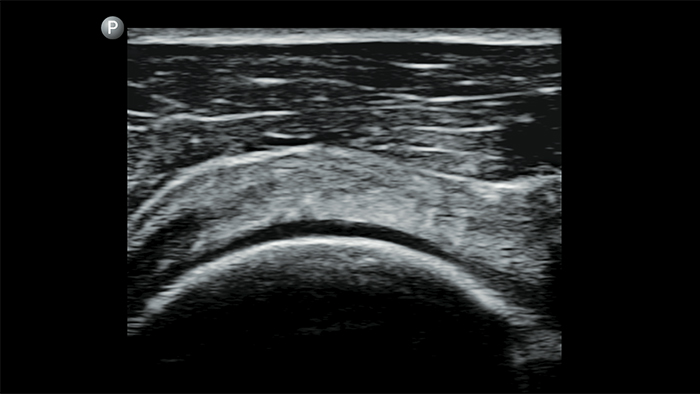

Breathe easier with Lumify

Lumify can help assess patients faster and improve accuracy when diagnosing common causes of dyspnea and other lung conditions.